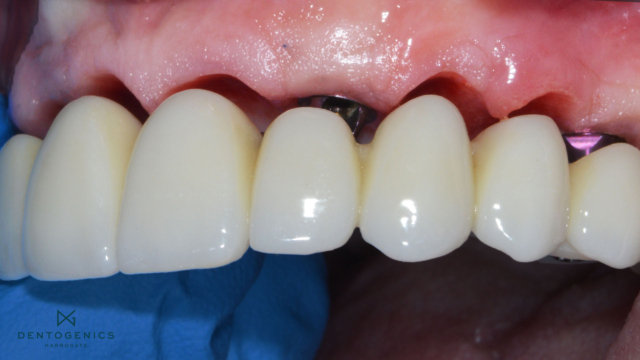

A top set of white teeth detaching from red gums.